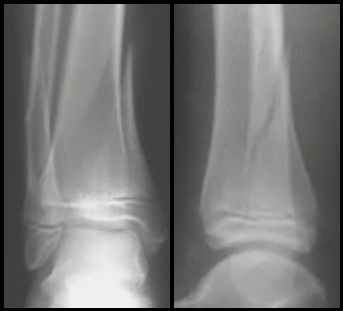

Tillaux

* Força de Rotação Externa

* Avulsão do tubérculo de Tillaux-Chaput pelo Tibiofibular Anterior - SH3 ou SH4

* 14 - 16 anos (Lembrar da ordem do fechamento da fise)